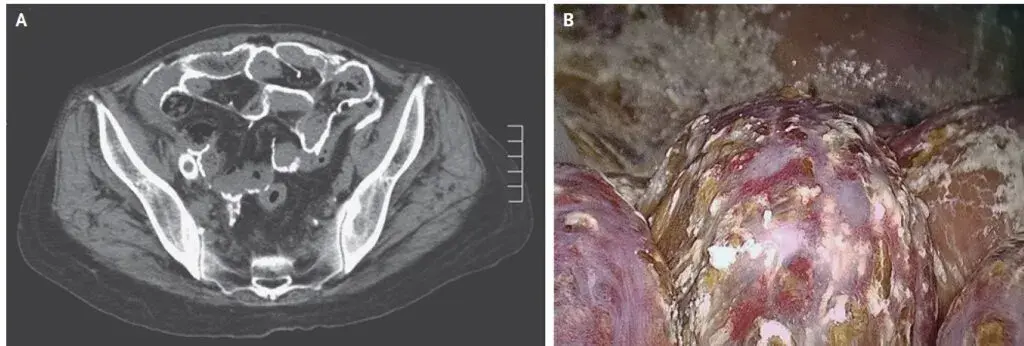

Realizado **TC de abdome** mostrou extensa calcificação do peritônio visceral e parietal (imagem A). Devido forte suspeita de **peritonite esclerosante encapsulante** foi realizado laparoscopia exploratória para confirmação diagnóstica. Pode-se observar um peritônio parietal muito espessado coberto por depósitos calcificados (imagem B). Aderências entre o peritônio e serosas inflamadas podem ser observadas.

O exame histopatológico mostrou fibrose e calcificação do peritônio parietal, sendo então confirmado o diagnóstico final de peritonite esclerosante encapsulante com extensa calcificações.